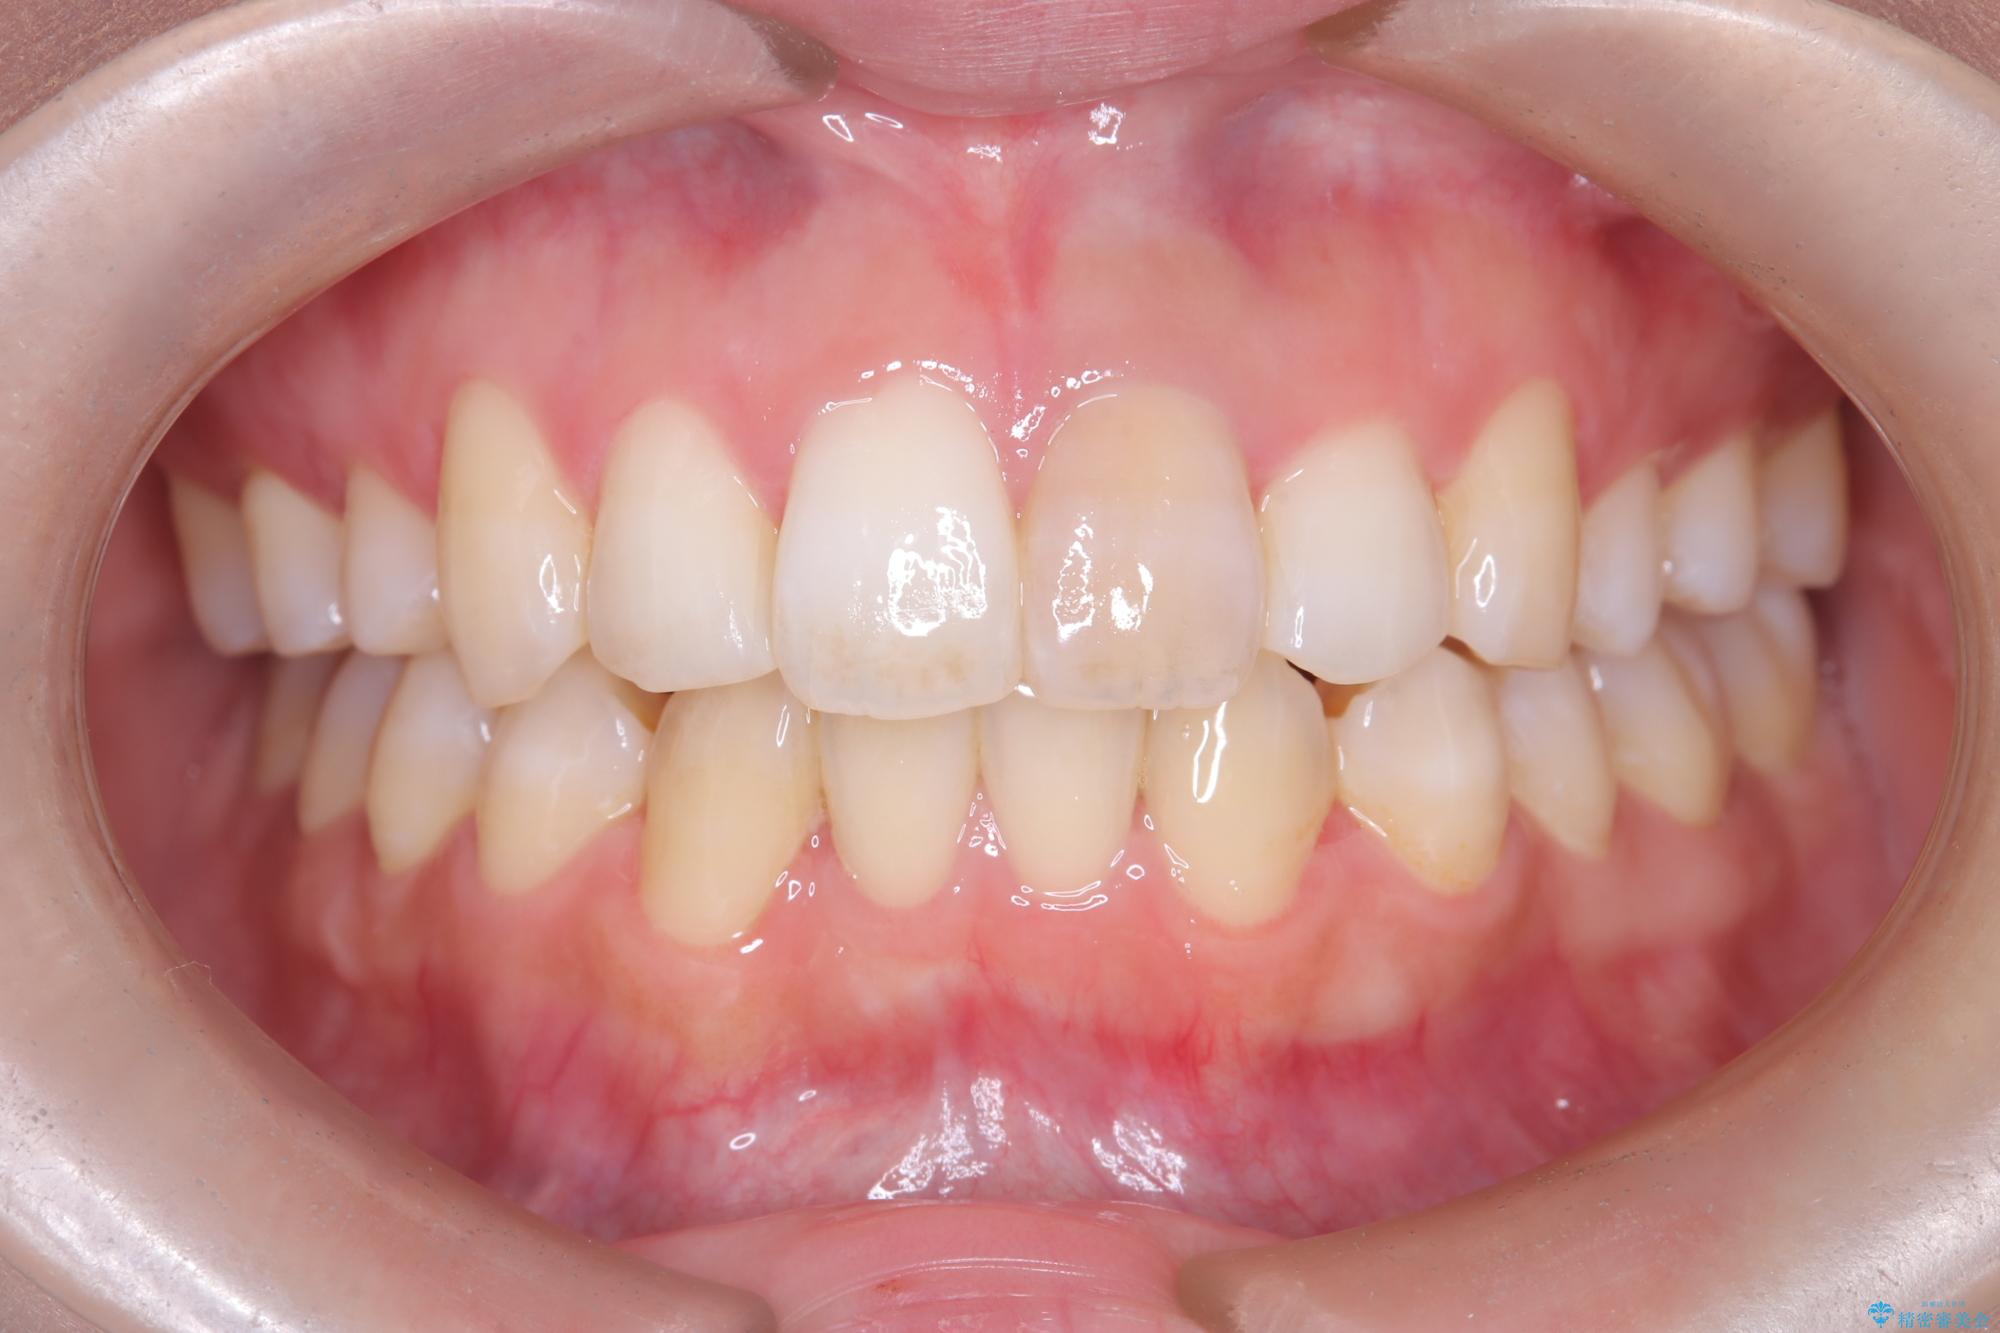

- 「以前、他院で神経を取った前歯がだんだん黒ずんできた」という見た目の改善を主訴にご来院されました。 診査の結果、神経を取り除いた後の歯(失活歯)特有の変色が起きており、さらに根の先端にわずかな影が見られたため、内部で感染が起きている可能性がありました。

そこで、まずは土台を外して根の内部をきれいにする再根管治療を行い、基礎をやり直した上で、透明感の高いオールセラミッククラウンで被せ直す治療計画を立案。単に白くするだけでなく、再発を防ぎ、長期的に美しい状態を保つことを目指しました。

オールセラミッククラウンによる修復: 最終的な被せ物には、一切の金属を使用しないオールセラミックを選択。隣の天然歯と色調や透明感を精密に合わせることで、どこを治療したかわからないほど自然な仕上がりとなりました。